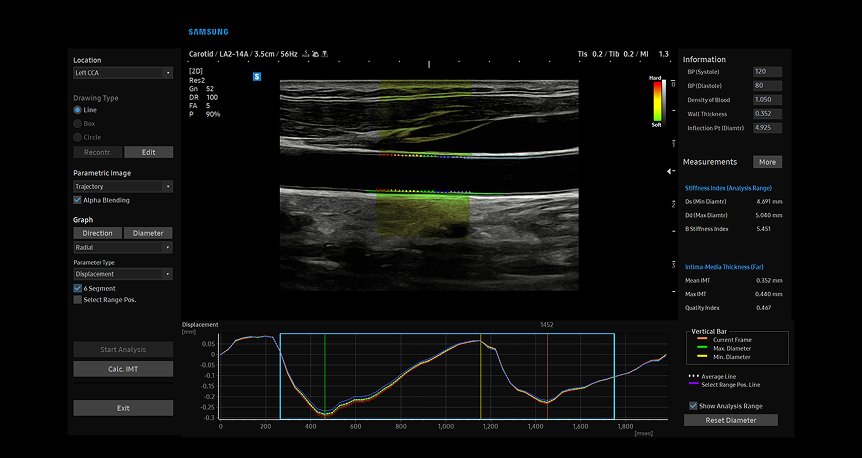

ArterialAnalysis™

ArterialAnalysis tool displaying advanced vascular assessment with highlighted carotid artery walls and corresponding pulse wave velocity measurements for early detection of arterial stiffness

ArterialAnalysis™ rileva i cambiamenti funzionali dei vasi, fornendo valori di misurazione come la rigidità, lo spessore intima-media e la velocità dell'onda di pulsazione dell'arteria carotide comune. Poiché i cambiamenti funzionali si verificano prima di quelli morfologici, questa tecnologia favorisce la diagnosi precoce delle malattie cardiovascolari.